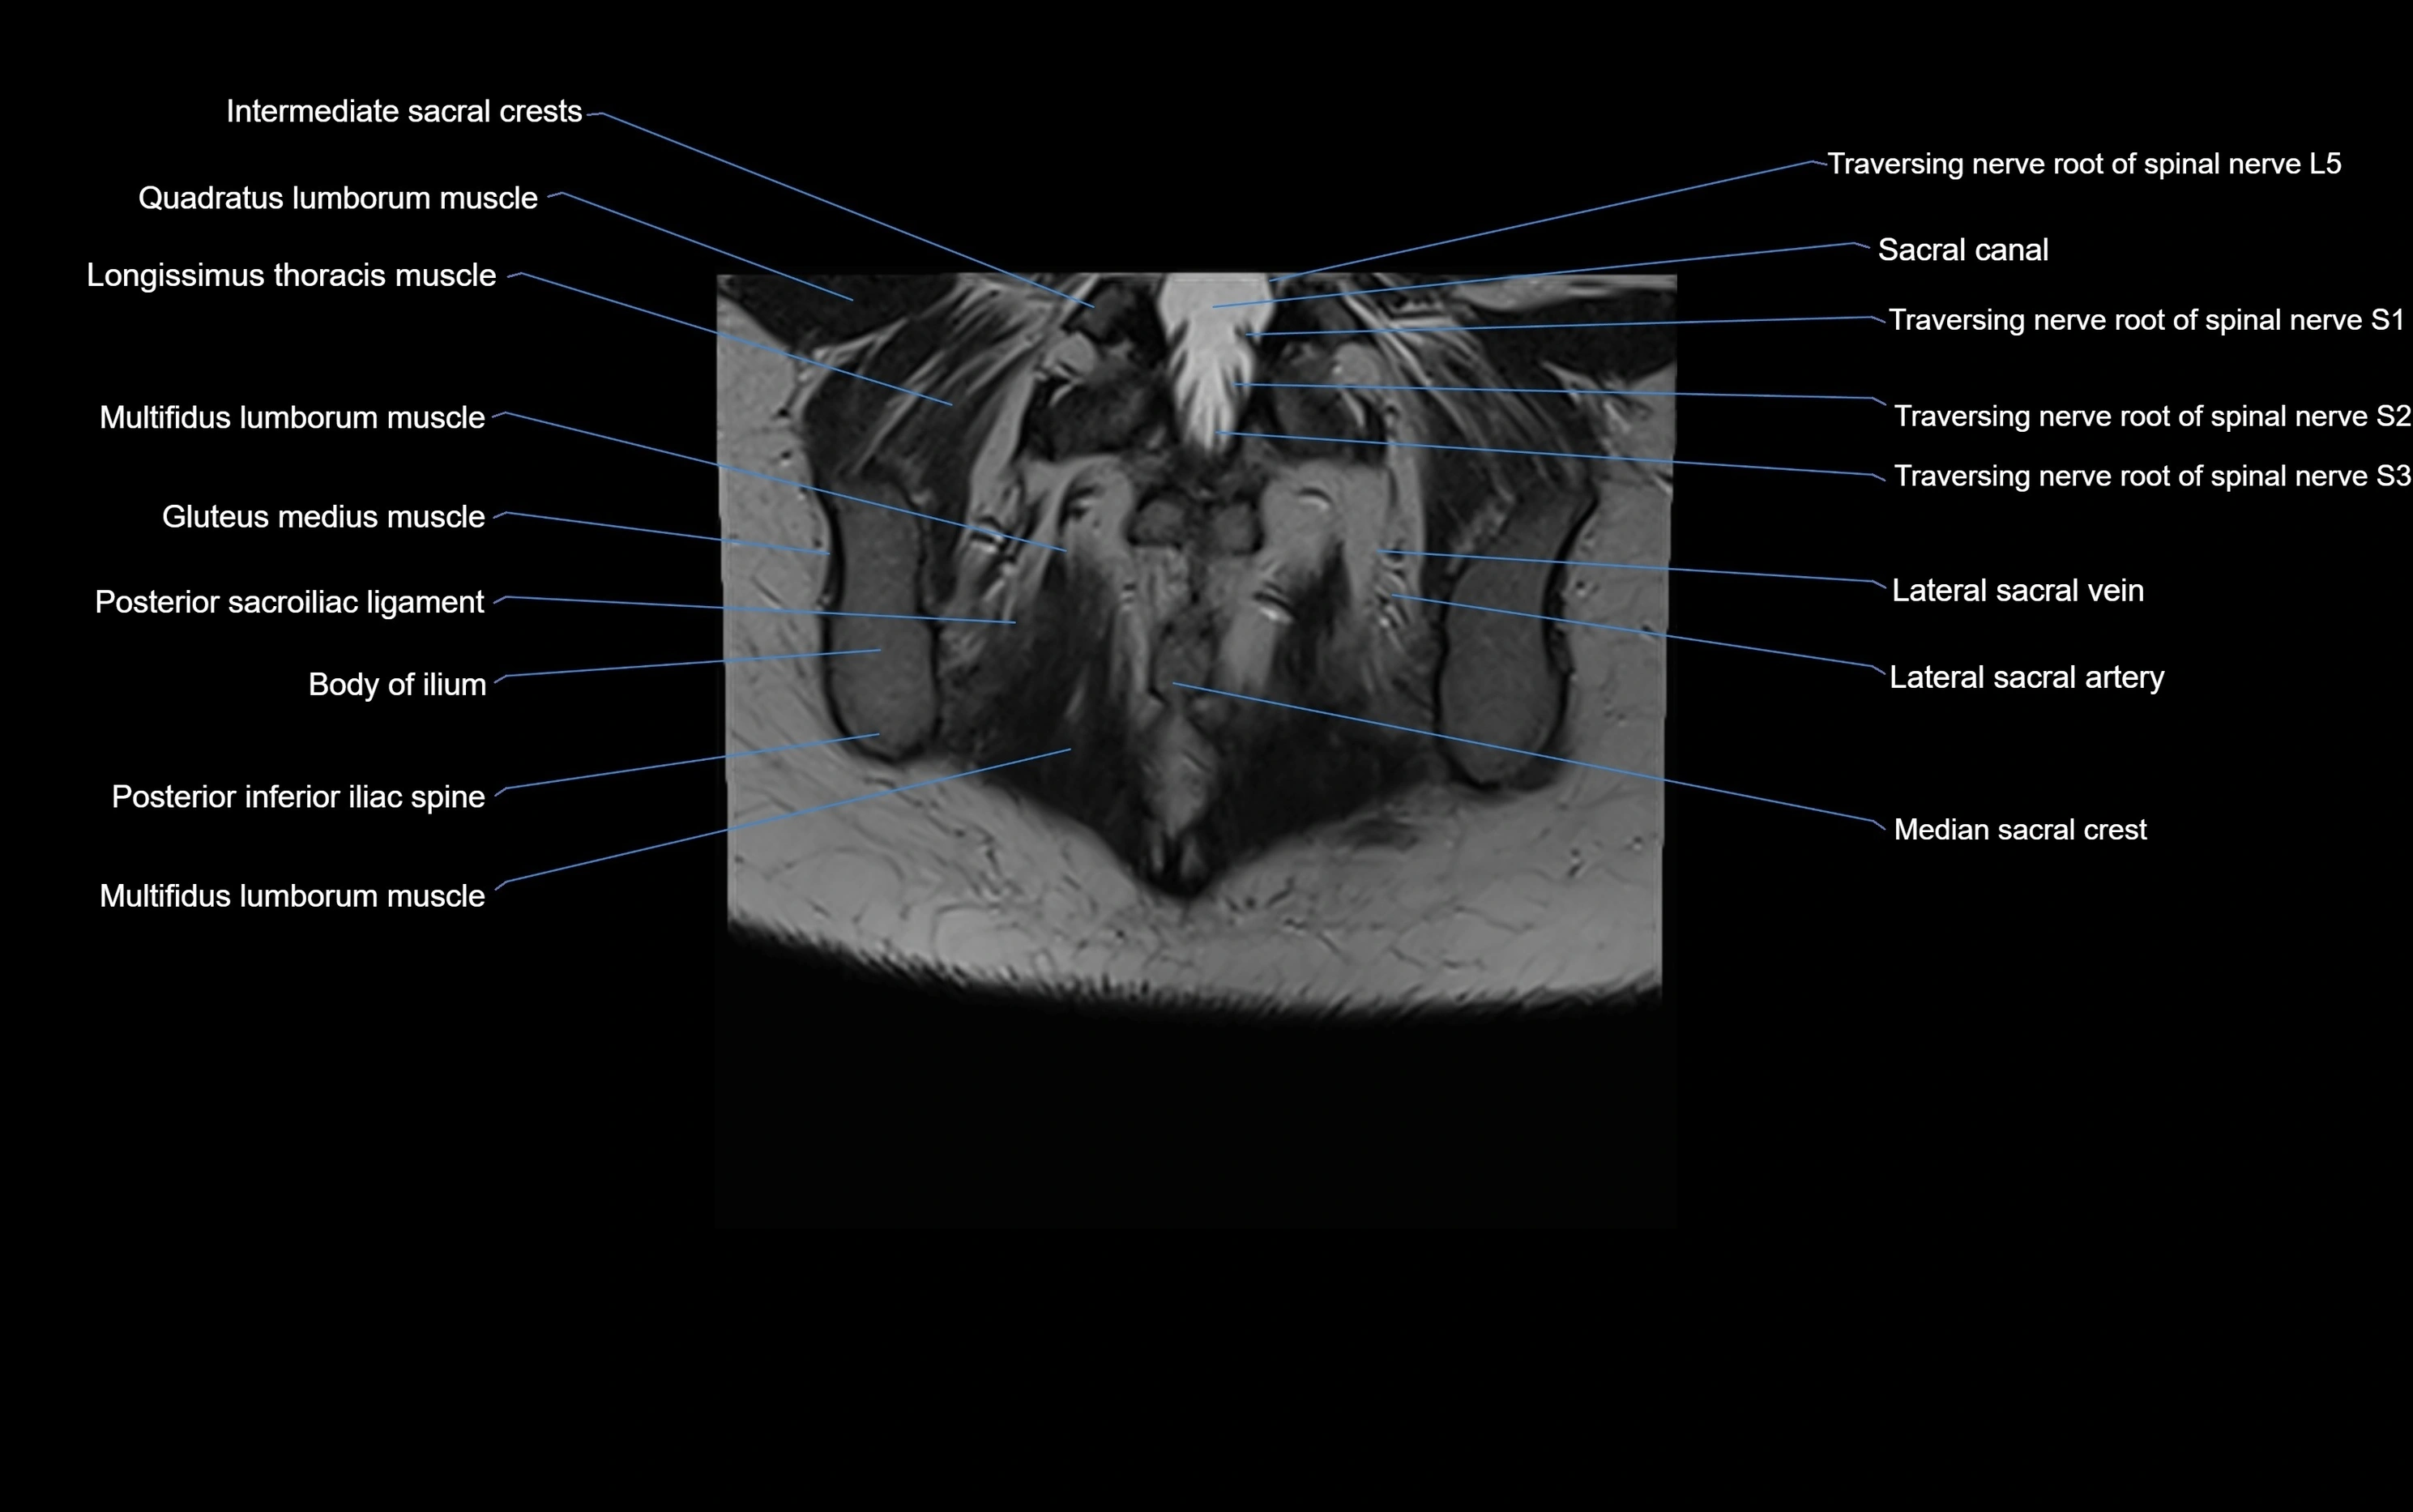

MRI image

image